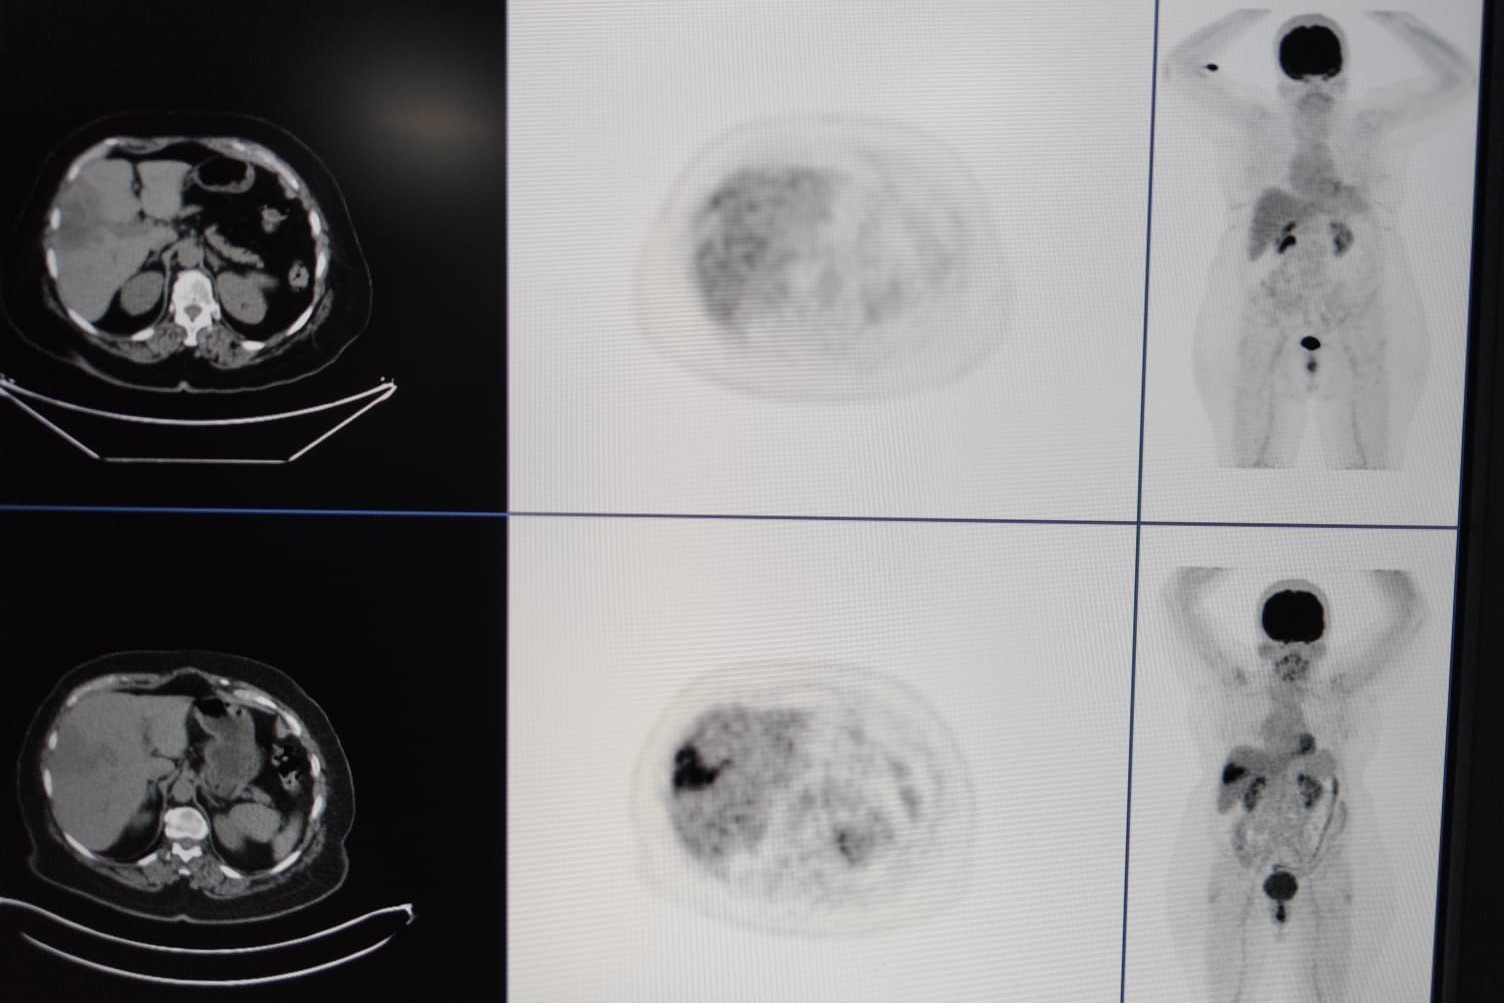

Nükleer tıp birimi ile işbirliği içerisinde hastalara tedavi uyguladıklarını ifade eden Şenol, “Bu servisimizde diğer birimlerle işbirliği yaparak çalışıyoruz. Nükleer tıp en fazla işbirliği yaptığımız birimdir. Hastaların çoğu buraya gelmeden nükleer tıp birimine görünüp öyle bize gelir. Hastanın uygunluğu araştırıldıktan sonra öncesinde burada tedavinin bir provası yapılır.

Kitlenin besleyici damarı bulunup buraya bir prova olarak asıl vereceğimiz ilaca benzer bir ilaçla enjeksiyon yapılıyor. Daha sora nükleer tıp biriminde ilacın o kitleyi ne kadar tuttuğu hesaplanıp uygun dozlarda asıl ilaç dozu hesaplanır.